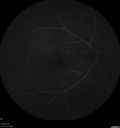

lung-jetop-082019.png

Metastatic Non Small Cell Lung Cancer to Choroid - Before External radiation535 views00000

lung-jetop-092019.png

Metastatic Non Small Cell Lung Cancer to Choroid - After External radiation603 views00000